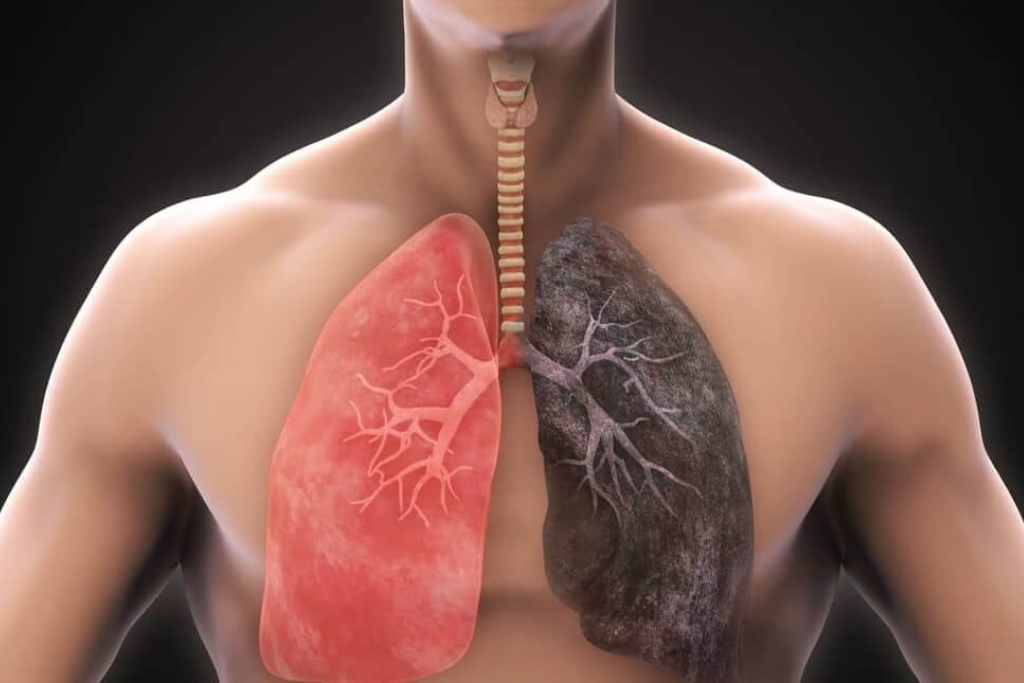

COPD Treatment

Chronic Obstructive Pulmonary Disease (COPD) is a long-term lung disease that causes persistent breathing problems due to airflow blockage.